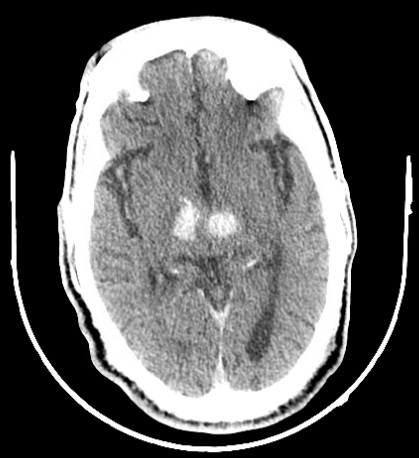

CT head revealed bilateral medial thalamic intracerebral hemorrhage, with right and left hemorrhages measuring 1.8×1×1.2cm and 1.3×1×1cm, respectively. CTA/CTV showed multivessel intracranial atherosclerotic disease without acute occlusion, no sign of arterial or venous vascular etiologic contribution. MRI redemonstrated bithalamic hemorrhages with tracking of edema and blood product into the brainstem, and no sign of underlying acute ischemic stroke.

During prolonged hospitalization, the patient developed complications including seizure, SIADH, bacterial pneumonia and Sar-CoV-2 infection. Gradually his condition worsened to an NIHSS of 16 at discharge and mRS of 4. Repeat CT head revealed interval increase in size of hematomas on the right (2.3x1.2x1.3cm) and on the left (1.3x0.9x1.4cm).